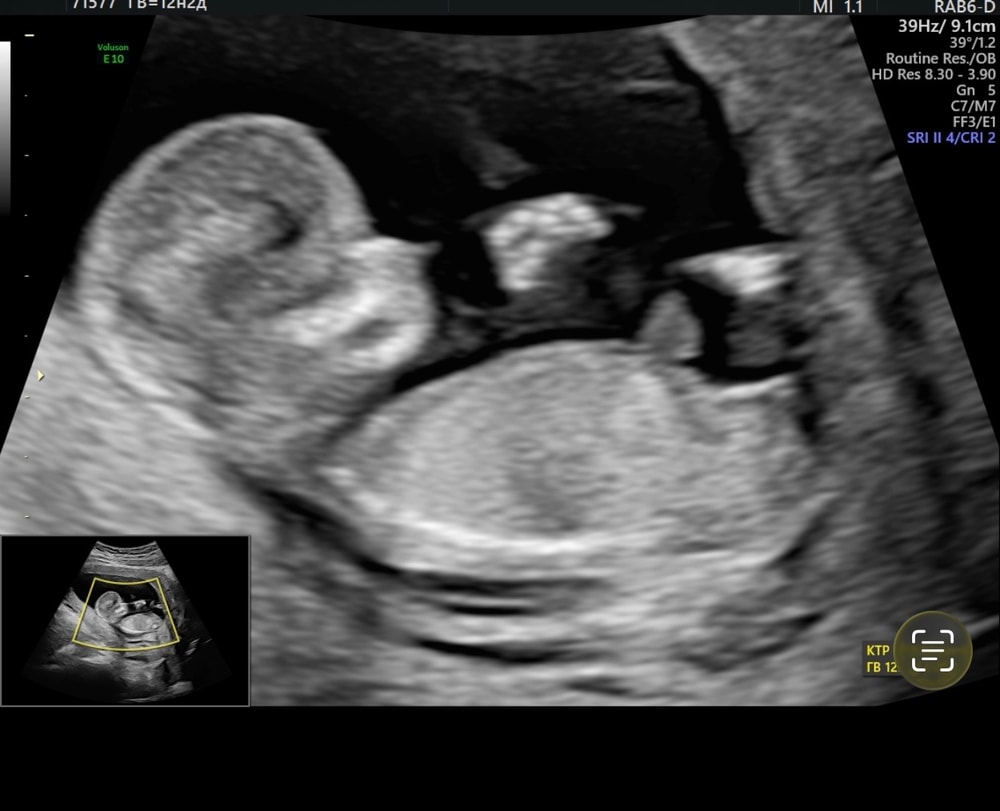

скрининг делала в центре медицины плода на ВО у Семенова А.Е , он работает на аппарате волюшин е8 ; но по моей просьбе мне провели исследование в другом кабинете на волюшин е10 , за что спасибо клинике и их клиентоориентированности … я теперь только к ним на узи 👍🏻✅

Я очень хорошо разбираюсь в половых бугорках , некий диванный эксперт на ББ 🤣 и знала , что скорее всего сюрприз для меня не получится , так и вышло , как только просветили ребенку бугорок , я увидела отчетливо свою девчушку 🎀 но промолчала … забыла предупредить доктора , чтоб он тоже молчал , честно , не думала , что на 1 скрининге вообще он может что-то сказать , да и этика , сначала спросить у родителей … но нет , в конце скрининга он тоже предположил девочку , тем самым супругу тоже стало известно … 🤦🏼♀️ а я привыкла , что у нас все идет вечно своим чередом , мы не из тех , кто может планировать что-то .. ну а в целом , говорят это не 100% , и доктор убедил нас , что все еще может поменяться , так что пока кружок не закрашиваю 🩷💙

Скрин из нашего видео с бугорком прилагаю … Ваши предположения и истории послушаю тоже с удовольствием 🌷 Ох эти гадания )